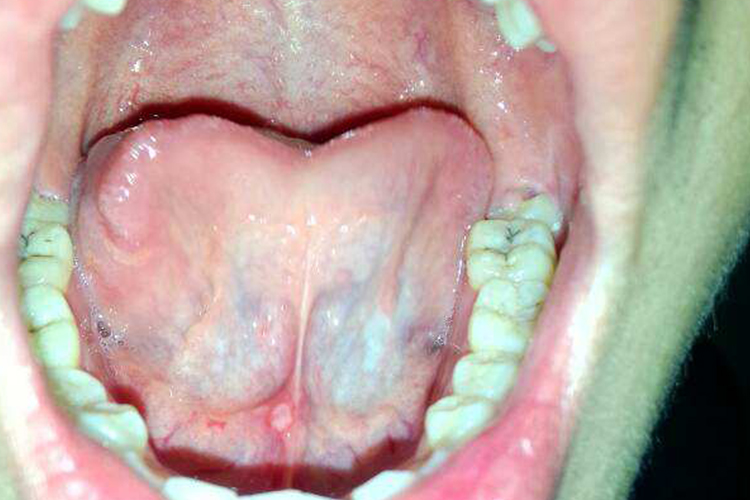

轻型阿弗他口腔溃疡、口腔白角化症、鹅口疮都可能会导致舌头下面有白色黏膜物,但具体症状有一定区别。

白角化症可发生在口腔黏膜的任何部位,以颊、唇、舌部多见。表现为灰白色或乳白色的边界不清的斑块或斑片,不高出或略高于黏膜表面,表面平滑、基底柔软无结节。与周围正常的黏膜相比,白角化区域黏膜的质地及弹性没有明显的变化。

鹅口疮主要表现为口腔黏膜表面出现白色或灰白色乳凝块样小点或小片状物,可逐渐融合成大片,不易拭去,若强行擦拭剥离后,局部黏膜潮红、粗糙、可有溢血。患处不痛,一般无全身症状。